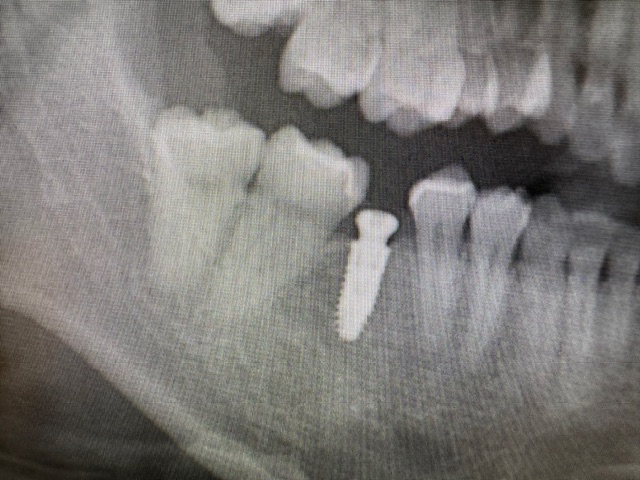

③インプラント 喪失した部分のみの骨の中にフィクスチャー埋入、固定式

(両隣在歯を削ることなく間に埋入)

(1回法、2回法とあり、1回法ではこの様にキャップで暫く過ごして頂きます)